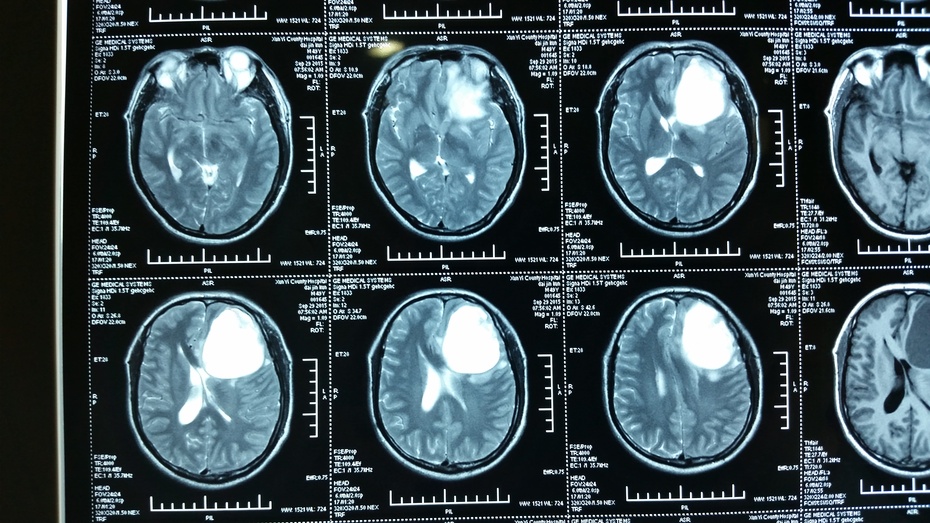

胼胝体胶质瘤

胼胝体胶质瘤一例